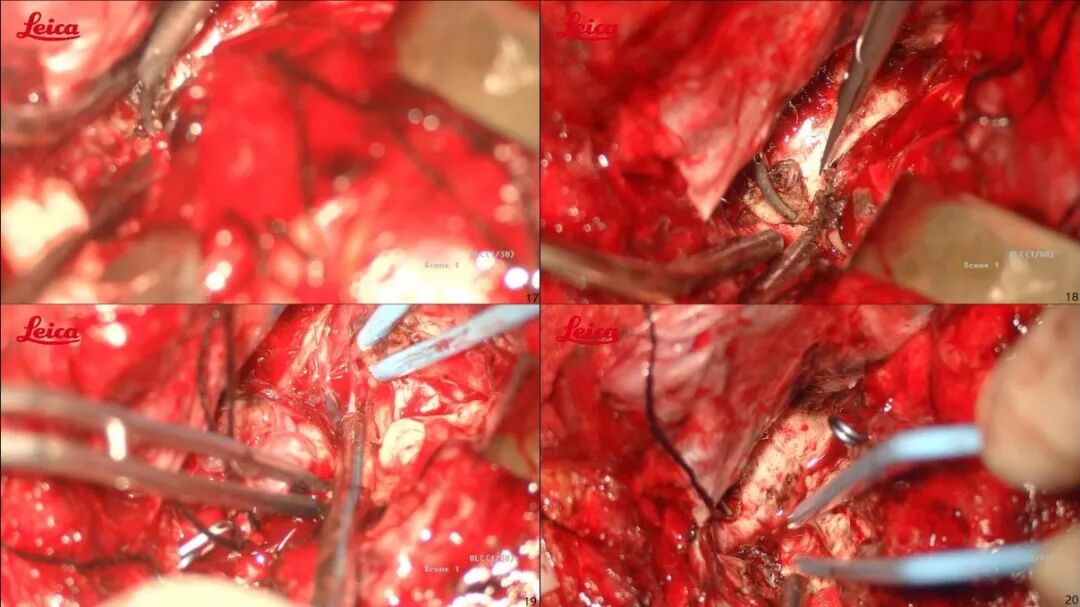

仰卧位,头偏右,取左侧额颞瓣;咬平蝶谷脊以充分暴露颅底(考虑瘘口供血动脉为颈外动脉颅底硬膜支、部分颈内动脉及侧裂动脉);为防止阻断动脉化静脉引起出血,先临时阻断可能责任供血动脉,待确定责任动脉后再将其离断,最后处理引流静脉;术中颅内压力高先清除部分血肿,动静脉瘘切除后将剩余血肿全部清除(见图3,术中截图)。因存在侧脑室及四脑室存在血肿,术中开放侧脑室,留置脑室外引流管(含压力测量)。

图3. 术中手术过程截图